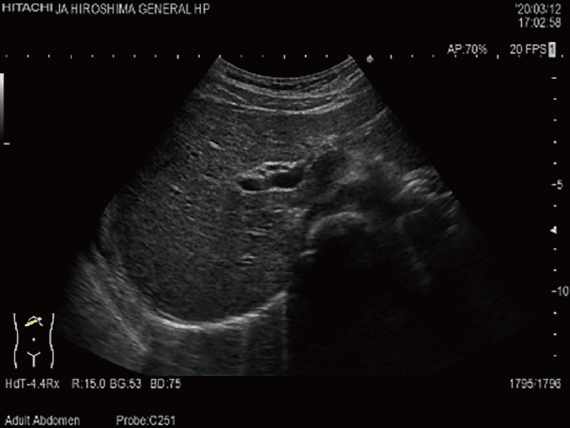

腹部超音波検査

腹部より超音波を照射して,肝臓・胆嚢・膵臓・脾臓・腎臓・大動脈などの腹腔内臓器を観察する検査です。各種臓器の腫瘍をはじめとして,結石,嚢胞,ポリープなどの発見や脂肪肝,肝炎,肝硬変などの各臓器の形態の評価に用いられます。